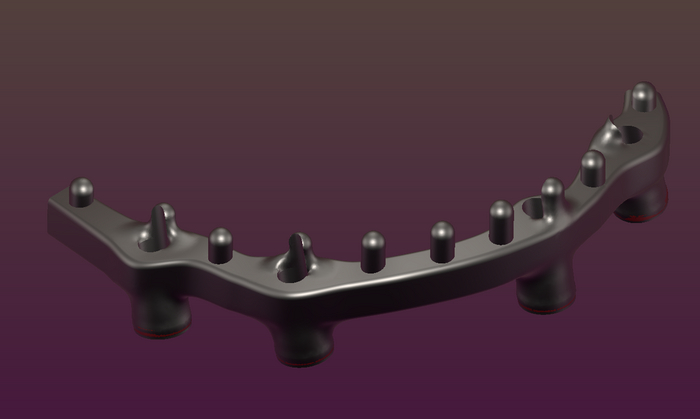

С восковой постановки зубов снимается "ключ" с помощью которого зубы переносятся на каркас.

Далее проверяю если не нарушилось положение зубов при переносе, моделирую форму десны будущих протезов, снимаю при помощи технического силикона формы в которые заливается пластмасса.

Полимер (порошок) и мономер (жидкость) взвешиваю на весах, получается жидкая смесь для заливки в формы. Процесс полимеризации (затвердевания) пластмассы протекает в воде и под давлением 2.5 атмосферы.